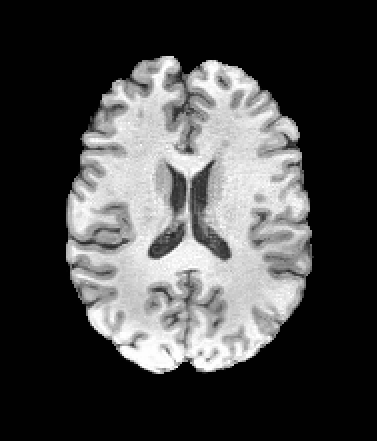

A trained MetaVoxel model can be unconditionally sampled by drawing Gaussian or categorical noise for each variable at timestep , and iteratively apply the denoising network until reaching . Unlike conventional diffusion models that focus solely on image generation, MetaVoxel can generate coherent synthetic patient profiles from the joint distribution , as shown in Figure 2.

| Age: 64.0 | Age: 53.8 | Age: 70.9 | Age: 76.9 |

| Sex: Male | Sex: Female | Sex: Female | Sex: Male |

![]() |

| Age: 80.9 | Age: 77.7 | Age: 73.2 | Age: 84.6 |

| Sex: Male | Sex: Female | Sex: Female | Sex: Female |